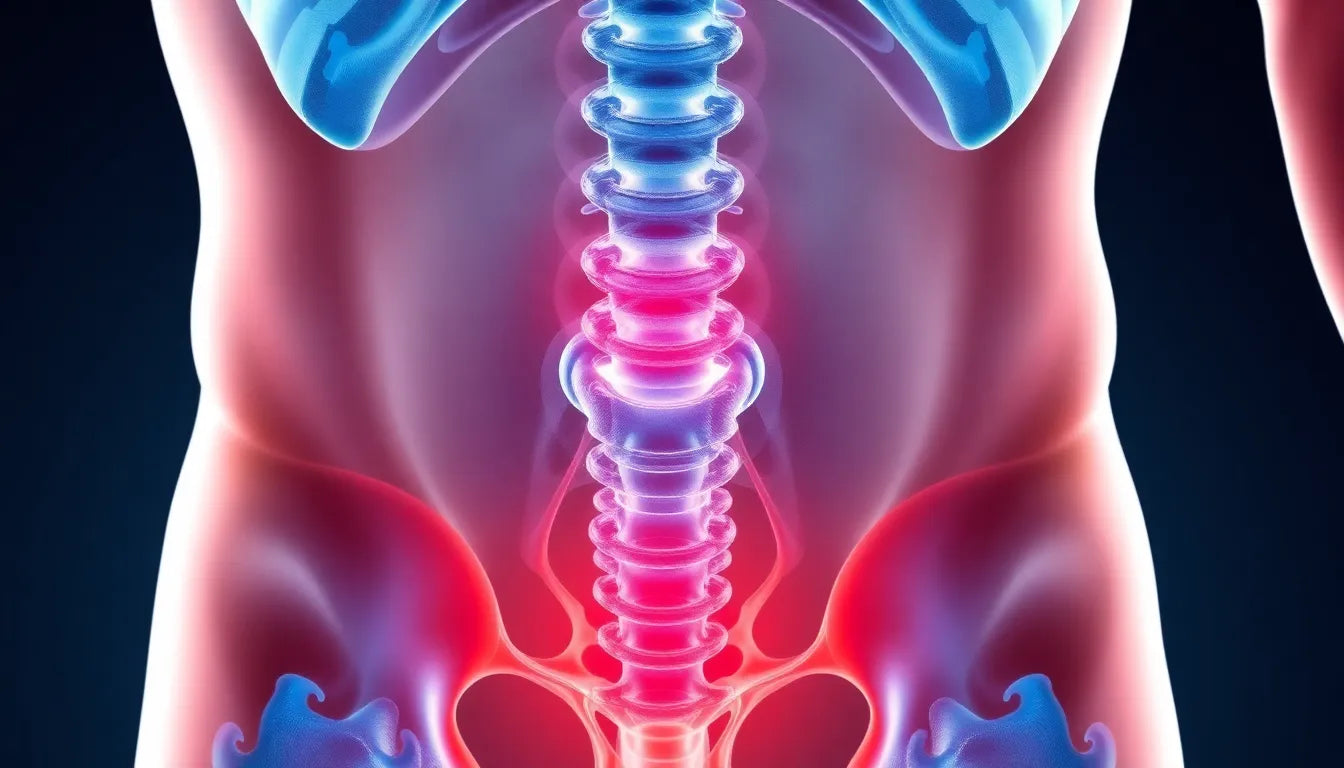

Een discus hernia, ook wel bekend als een hernia nuclei pulposi, is een veelvoorkomende oorzaak van rugpijn die aanzienlijke impact kan hebben op het dagelijks leven. Deze aandoening treedt op wanneer de zachte kern van een tussenwervelschijf door een scheur in de harde buitenlaag naar buiten puilt. Dit kan leiden tot irritatie van nabijgelegen zenuwen, wat resulteert in pijn, gevoelloosheid of zwakte in de ledematen. Het begrijpen van de aard van een discus hernia is cruciaal voor iedereen die te maken heeft met onverklaarbare rugpijn.

Een discus hernia, ook wel bekend als een hernia nuclei pulposi, is een veelvoorkomende oorzaak van rugpijn die aanzienlijke impact kan hebben op het dagelijks leven. Deze aandoening treedt op wanneer de zachte kern van een tussenwervelschijf door een scheur in de harde buitenlaag naar buiten puilt. Dit kan leiden tot irritatie van nabijgelegen zenuwen, wat resulteert in pijn, gevoelloosheid of zwakte in de ledematen. Het begrijpen van de aard van een discus hernia is cruciaal voor iedereen die te maken heeft met onverklaarbare rugpijn.

Een discus hernia ontstaat vaak door leeftijdsgebonden degeneratie van de tussenwervelschijven. Naarmate we ouder worden, verliezen de schijven hun vochtgehalte, waardoor ze minder flexibel en vatbaarder voor scheuren worden. Naast veroudering kunnen acute letsels, zoals vallen of zwaar tillen, ook bijdragen aan het ontstaan van een hernia. Deze plotselinge belasting kan de schijf onder druk zetten, wat leidt tot een scheur en het uitpuilen van de kern.

De symptomen van een discus hernia variëren afhankelijk van de locatie van de hernia en de ernst ervan. Veelvoorkomende symptomen zijn onder andere pijn in de onderrug of nek, die kan uitstralen naar de armen of benen. Dit komt doordat de uitpuilende schijf de nabijgelegen zenuwen kan irriteren. Andere symptomen zijn gevoelloosheid of tintelingen in de ledematen en spierzwakte, wat kan leiden tot verminderde mobiliteit en kracht.